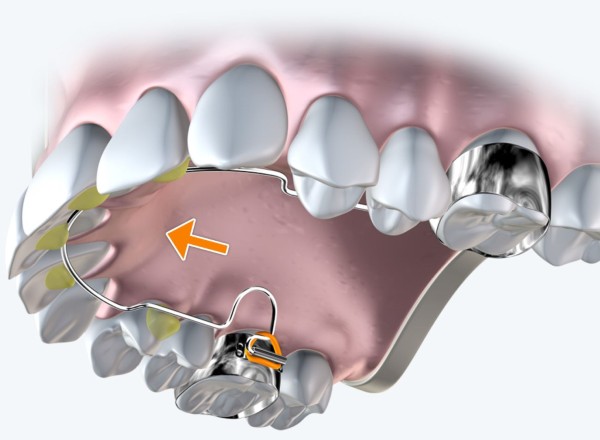

Nong hàm bằng dây cung

Trong phương pháp này, các dây cung nha khoa được nắn chỉnh để tạo lực kéo mở rộng hàm. Đây là kỹ thuật đơn giản nhưng đòi hỏi kỹ năng và kinh nghiệm của bác sĩ để điều chỉnh lực phù hợp, tránh gây đau hoặc tổn thương cho bệnh nhân.

Dây cung thường được nối với các brackets gắn trên răng, sau mỗi lần chỉnh, khí cụ sẽ tạo ra lực kéo tác động vào xương hàm, từ đó thúc đẩy quá trình mở rộng diễn ra hiệu quả.

Phương pháp này phù hợp với những trường hợp nhẹ, hoặc kết hợp với các thủ thuật khác để nâng cao hiệu quả chỉnh hình. Đồng thời, bệnh nhân cần phối hợp tốt trong việc chăm sóc vệ sinh trong quá trình điều trị.